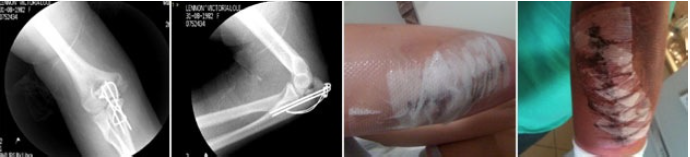

Victoria – Reconstruction

After badly breaking my elbow in a biking accident, I underwent a full reconstruction surgery along with wire and pins fitted to my elbow joint. I sought assistance from Matt approximately 6 months post surgery to relieve pain in my elbow and associated pain in my neck, back and shoulder. In addition to this, I had limited mobility and nerve injury in the joint. Matt was able to identify and treat these areas extremely effectively due to his in depth knowledge of the human body and muscular-skeletal therapies.

Following my first reconstruction, Matt treated me on a monthly basis to assist with movement, mobility and pain management through manipulation and myofascial release of muscles. I required a second reconstruction to remove pins and wires and further reconstruct the joint after sustaining such serious injury initially. Matt assisted in release and preparation both physically and mentally before surgery and post surgery care. After the initial injury, my confidence had suffered also. Post surgery, Matt assisted with movement, massage and muscle release. I had extensive bruising and pain from the surgery and Matt’s techniques and treatment significantly improved my recovery timeframe and healing, particularly in comparison to my first reconstruction. Matt has been a key ingredient in my successful recovery both physically and emotionally. I have found him to be a knowledgable and dedicated professional and would not have such good results should I have been without his expertise and care.